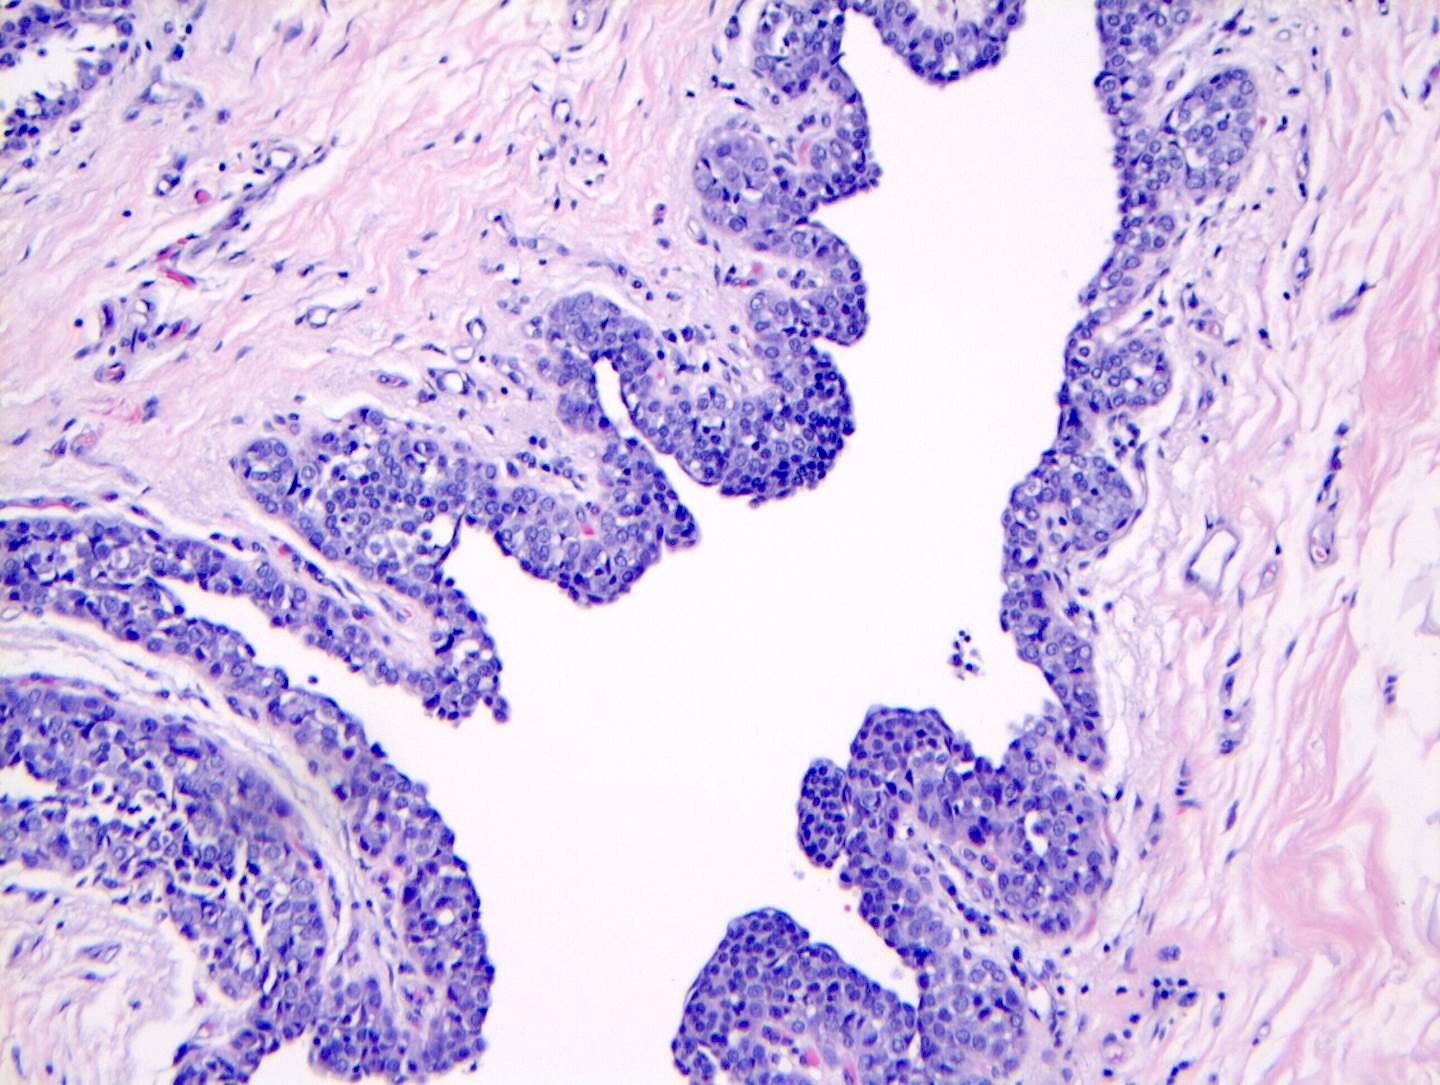

Microscopic (histologic) images

Contributed by Anna Biernacka, M.D., Ph.D.

- LCIS most often involves lobules but may also grow along the basement membrane of ducts (i.e., pagetoid spread)

- Pagetoid spread in ducts is the characteristic growth of cells between luminal and myoepithelial layers of a duct without destroying ductal epithelium or filling up ductal lumina

- Often makes the ducts appear convoluted; this is called a cloverleaf pattern

- Classic LCIS cells are monomorphic, evenly spaced, loosely cohesive and do not show polarization or gland formation

- Cytoplasm of LCIS cells is typically pale to lightly eosinophilic with indistinct cell borders

- In almost all cases of LCIS, at least some cells contain intracytoplasmic vacuoles or lumina, which may contain an eosinophilic globule; this feature is not specific to LCIS

- Outer layer of myoepithelial cells is retained in the acini and ducts involved but it may be attenuated